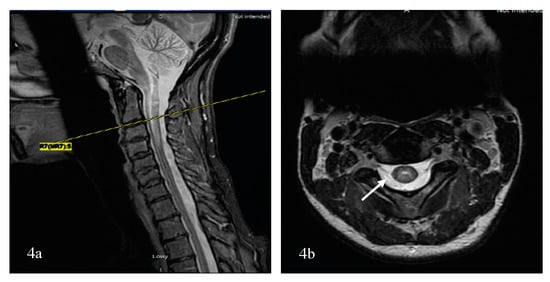

5.2.4. Imaging Patterns of Neuromyelitis Optica Spectrum Disorder-Associated Transverse Myelitis (NMOSD-TM)

Linear Lesions in NMOSD

Bright Spotty Lesions (BSLs) in Neuromyelitis Optica Spectrum Disorder